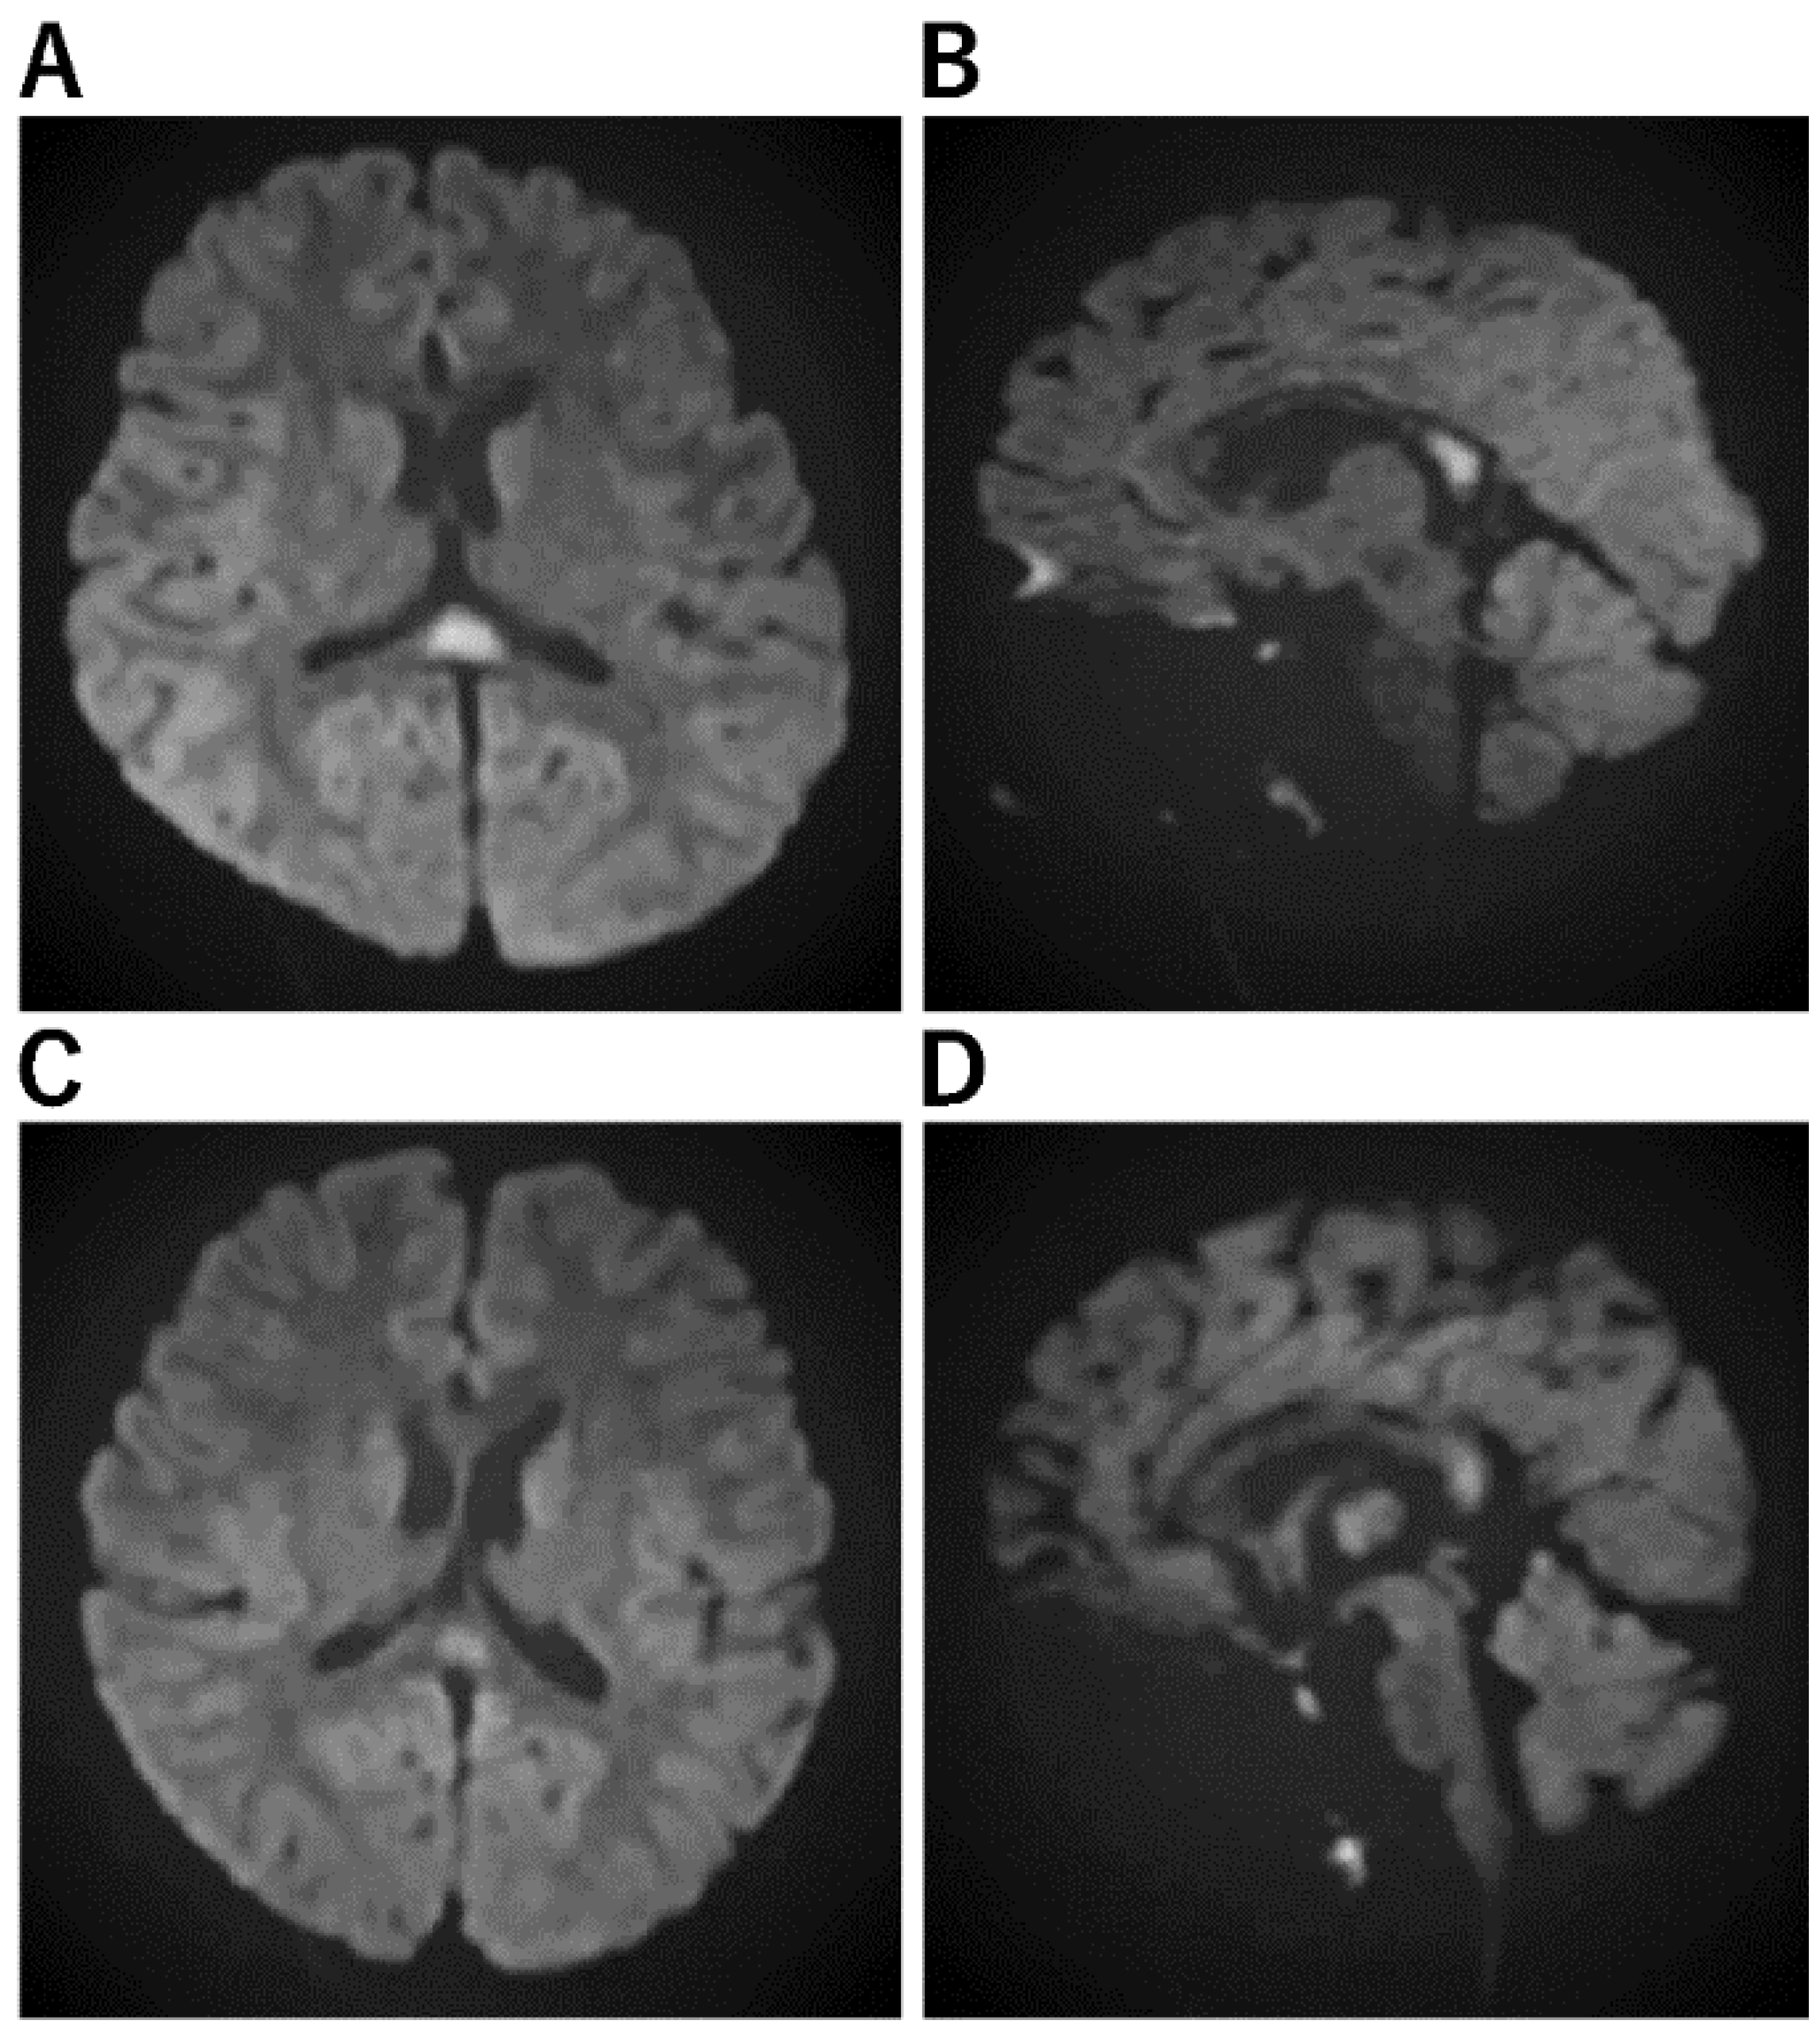

| Acute encephalopathy with biphasic seizures and late reduced diffusion (AESD) [29,48,49,50] | a. No abnormal lesion within 2 days. b. Subcortical white matter lesions between days 3 and 9, which are most obvious on DWI (bright tree appearance). The lesions are predominantly frontal or frontoparietal in a location with sparing of the peri-Rolandic region (central sparing). c. After 9 days, the bright tree appearance on DWI has disappeared, and T2WI or FLAIR imaging show high-intensity lesions with central sparing, and cerebral atrophy. d. MRS shows acute Glu elevation (days 1–4), changing to subacute Gln elevation (days 4–12). e. Cranial MRI in the late phase shows cerebral cortical lesions of reduced diffusion, indicating cellular edema of the subcortical white matter. |

| AESD [78,79] | ||||

| Biphasic seizure and altered consciousness during the acute phase, followed by restricted diffusion in bilateral cerebral parenchyma on MRI during the subacute stage | Incidence is higher in Asian countries, especially Japan, and the genetic background may be a possible higher incidence | A prolonged febrile seizure is the first symptom. Brief seizures may be present in mild cases. Involuntary movements may act prognostic factor AESD prediction score by Tada et al. [80] Level of consciousness 12–24 h after seizure GCS 14–13 (JCS 1–3) and GCS 12–9 (JCS 10–30) were scored 2, GCS 8–3 (JCS 100–300) scored 3, age below 1.5 years scored 1, duration of ES above 40 min scored 1, mechanical intubation scored 1, AST on admission above 40 mEq/l scored 1, blood glucose on admission above 200 mg/dl scored 1, and Cr on admission above 0.35 scored 1 AESD prediction score by Yokochi et al. [81] pH < 7.014 1 point ALT ≥ 28 2 points Glu ≥ 228 2 points Time to awakening ≥ 11 h 2 points Cre ≥ 0.3 1 point Ammonia ≥ 125 2 points 4 points or more: High-risk group for AESD for both scores [77,78] | High signal intensity on DWI for the anterior area Severe acidosis is the most common lab finding. EEG may usefully differentiate AESD from PFS | Cyclosporine, methylprednisolone pulse therapy, intravenous immunoglobulin, and other therapies that suppress inflammatory cytokines. TTM may be considered but need to differentiate AESD from FSE at the early acute stage. TTM during the prolonged convulsive phase, prior to the diagnosis of AESD, could prevent the patient from developing a second phase of convulsions and thus prevent the patient from developing AESD. |